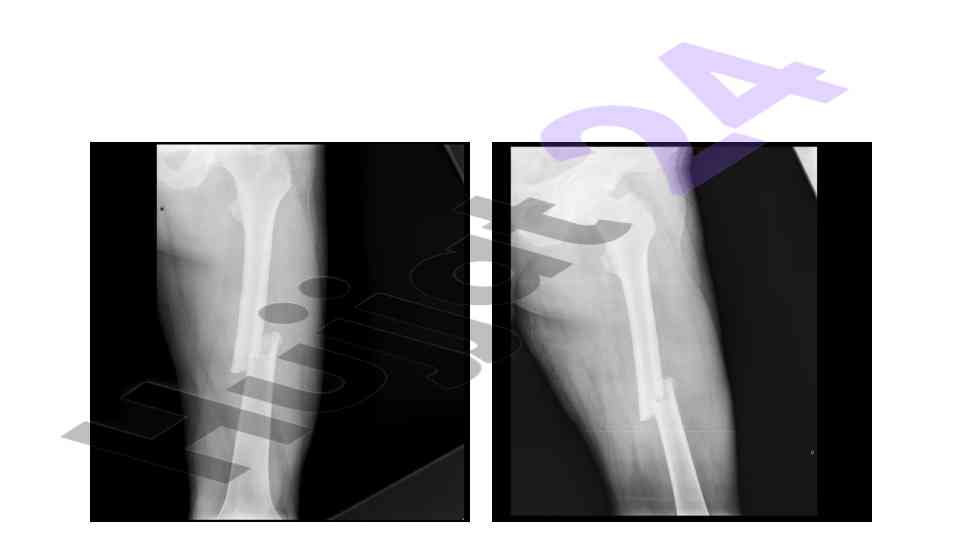

An overview of the muskuloskeletal system with a focus on pediatric applications and implications for treatment.